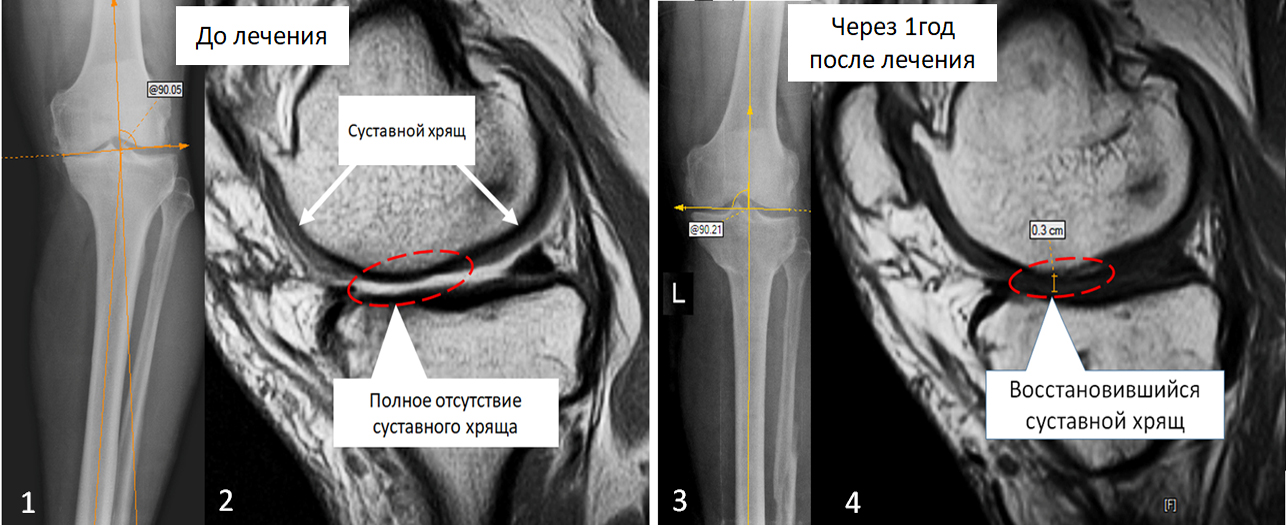

До начала лечения. На рентгенограмме  (1) - выраженная варусная деформация большеберцовой кости. На МРТ снимках (2) – имеется участок суставной поверхности с полным отсутствие суставного хряща (обведено пунктирной линией), на месте хряща определяется суставная жидкость. В норме суставной хрящ выглядит как широкая серая полоса (указано стрелками).

Нами было проведено восстановительное оперативное лечение с использованием аутологичных мезенхимальных стволовых клеток.

Через один год после оперативного лечения. На рентгенограмме (3) - ось большеберцовой кости восстановлена. На МРТ снимках (4) – на месте отсутствовавшего ранее суставного хряща образовался новый хрящ толщиной до 3 мм (обведено пунктирной линией).